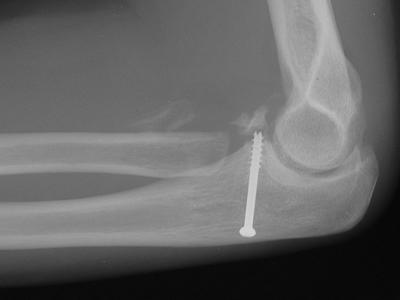

Initial fixation: radial head excision and coronoid screw fixation. In this case, a lag screw was used, but threads bridged the fracture line, preventing compression.